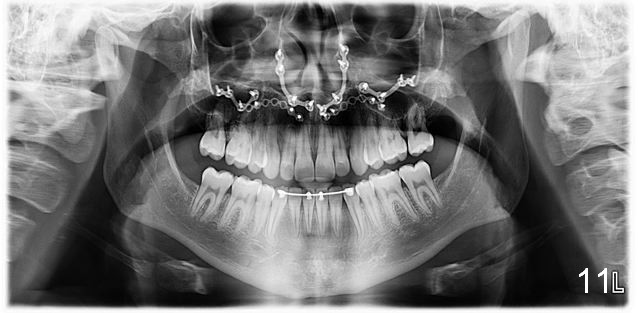

Final photos are taken on 03/23/2016. Mid face deficiency improved, now just a hint (Fig.3). Before (Fig.4,10) and after (Fig.5-9) occlusal adjustment of the canines.

BTW: Philip reports a life changing event! Why? Not just because he can chew his food better and has improved appearance, but he can breathe as a result of maxillary expansion and advancement. He said that his only regret was that he did not correct it sooner;-) He had seen allergists, ENTs, and pulmonologists prior to orthodontics and surgery.